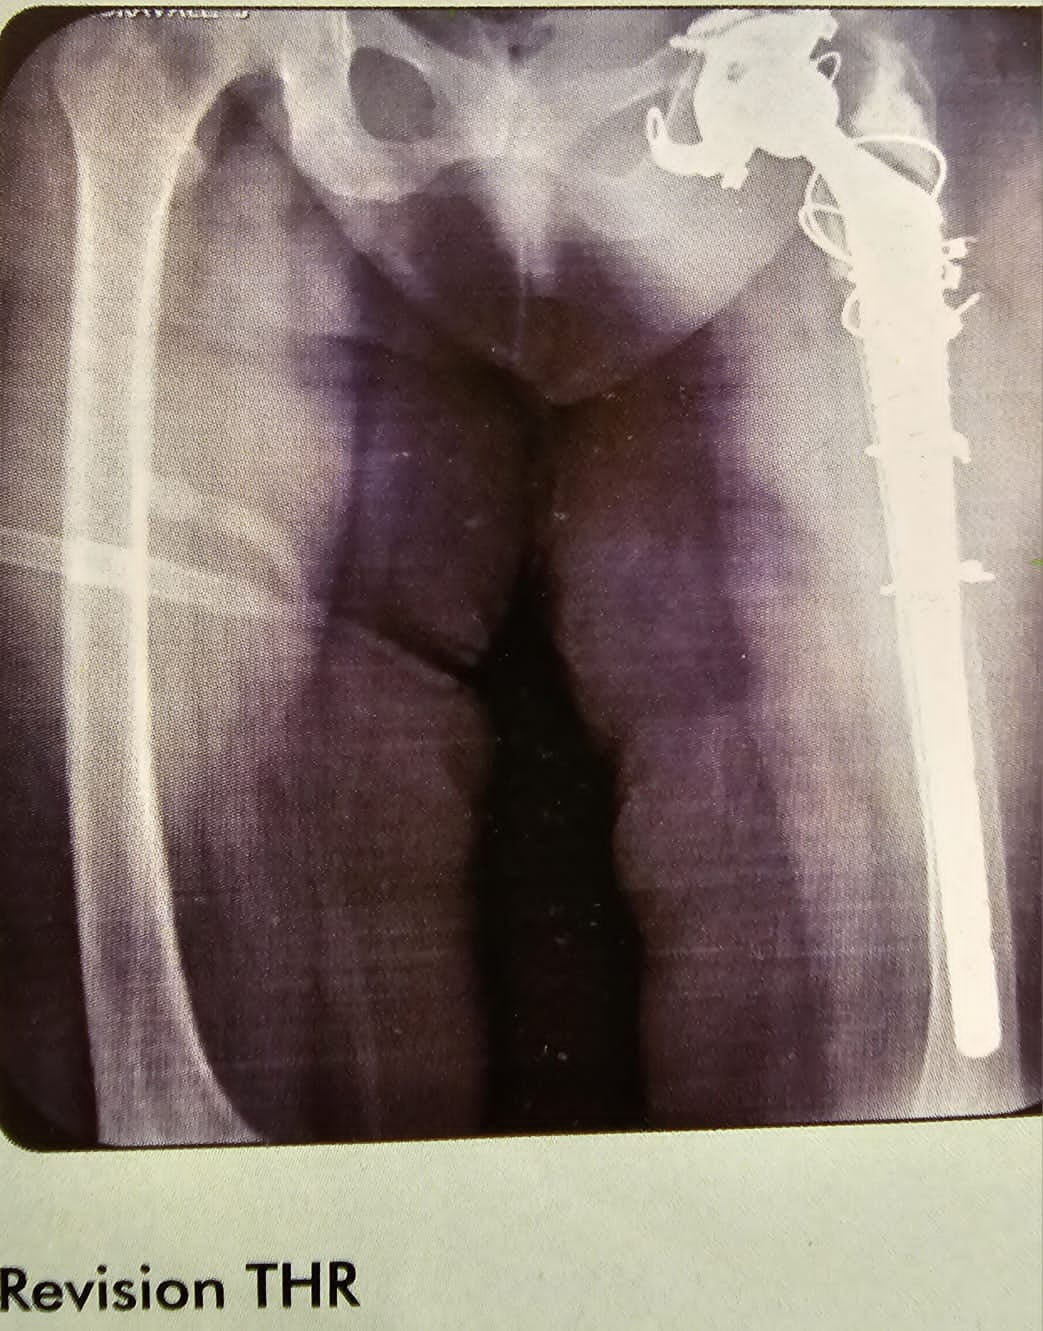

Revision THR

This is the case of revision of THR, extended trochanteric osteotomy, of the femur and put multiple circulage wires to reduce it. And also circulage wires for the GT. Have used a shell and fixed with screws and the lower end was turned into operator foramin, 36 mm head un cemented . The patient did very well.